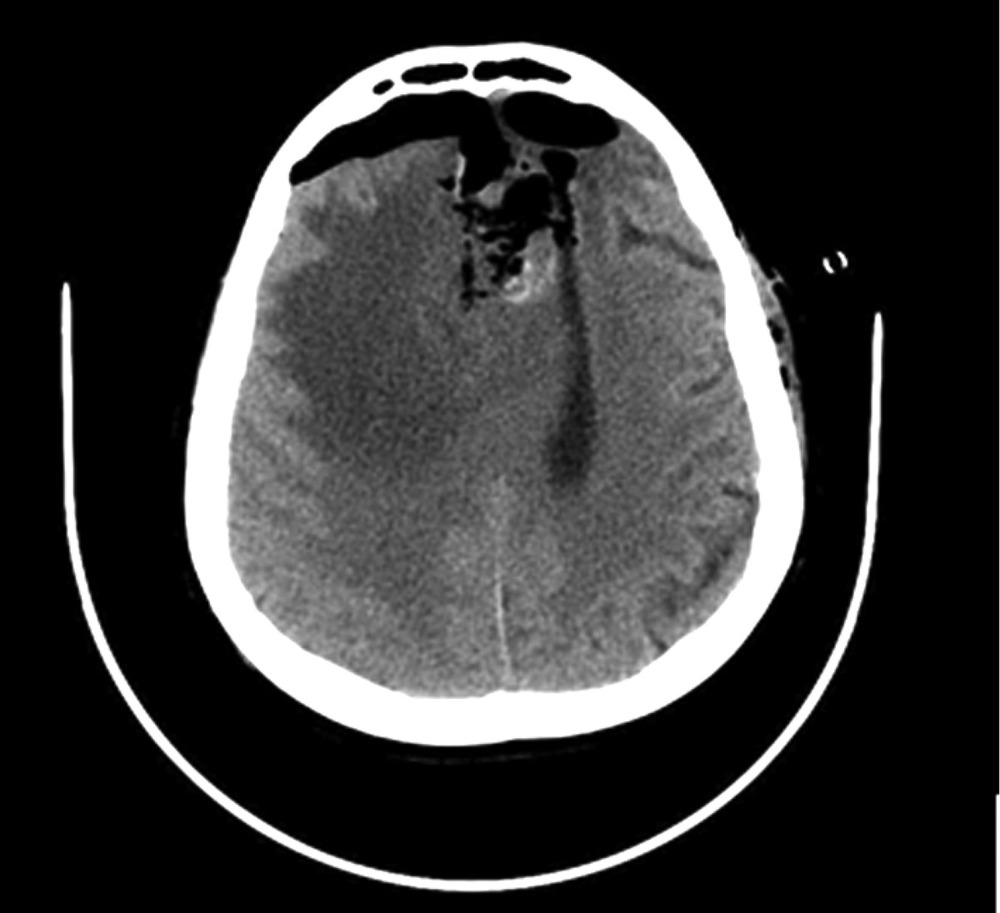

Наблюдение 2. Пациентка 64 лет за 10 мес до настоящей госпитализации была оперирована и проходила комбинированное лечение по поводу глиобластомы (Grade IV) левой лобной доли. В течение всего срока заболевания приступов с нарушением сознания или иных пароксизмальных состояний не наблюдалось. Противосудорожную терапию не получала. При контрольной МРТ за 3 нед до госпитализации выявлено увеличение размеров опухоли. Принято решение о повторном хирургическом вмешательстве. После операции 14.03.16 пациентка была переведена в палату пробуждения, где спустя 1,5 ч на фоне выхода из наркозного сна развился вторичный генерализованный судорожный приступ, который самостоятельно купировался в течение 1 мин. Проведенное КТ-исследование выявило послеоперационные изменения и отсутствие хирургических осложнений (рис. 5). В ходе суточного видео-ЭЭГ-мониторинга были выявлены диффузные изменения биопотенциалов в виде умеренновыраженной дезорганизации корковой активности, при отсутствии типичных эпилептиформных потенциалов (рис. 6). Было принято решение не назначать больной противосудорожную терапию и оставить ее на сутки под наблюдением в отделении реанимации. Клинических приступов или иных пароксизмальных проявлений не отмечено, при видео-ЭЭГ-мониторинге эпилептиформная активность не зафиксирована. После перевода в клиническое отделение приступов также не наблюдалось. Спустя 8 дней после операции пациентка в удовлетворительном состоянии выписана для продолжения химиотерапии по месту жительства.

Рис. 5. Наблюдение 2. СКТ в 1-е часы после удаления опухоли левой лобной доли. Послеоперационные изменения с зоной перифокального отека, скопления воздуха и небольшой зоной имбибиции кровью в области операции.